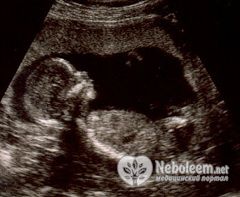

Если сделать УЗИ на 33 неделе беременности, то можно определить размеры будущего ребенка. Его длина составляет где-то 41 – 42 см, весит он от 1800 до 2200 г. В течение нескольких недель прибавки в весе ребенка будут довольно интенсивными.

По УЗИ на 33 неделе беременности можно заметить, что тело плода стало пропорциональное и больше похоже на новорожденного. Несмотря на компактную эмбриональную позу, ему все же стало тесновато в полости матки, поэтому движения его ощущаются в животе на 33 неделе беременности реже, но стали более сильными. Довольно много времени плод проводит во сне, но отсутствие шевелений в течение 12 часов – опасный прогностический признак для дальнейшей беременности.

На 33 неделе беременности будущий ребенок уже занимает свою постоянную позицию. Оптимальной является положение головкой вниз, но могут встречаться и такие разновидности, как тазовое, ножное и даже поперечное предлежание. Чтобы плод занял правильное предлежание, врач рекомендует комплекс специальных физических упражнений для женщины. Спать для этого тоже желательно преимущественно на левом боку.

Врач направляет женщину на УЗИ на 33 неделе беременности в том случае, если она не сделала его до этого срока, в 30 – 32 недели. При необходимости возможно проведение кардиотокографии, с помощью которой можно оценить, как меняются сокращения плода в ответ на мышечное напряжение матки.